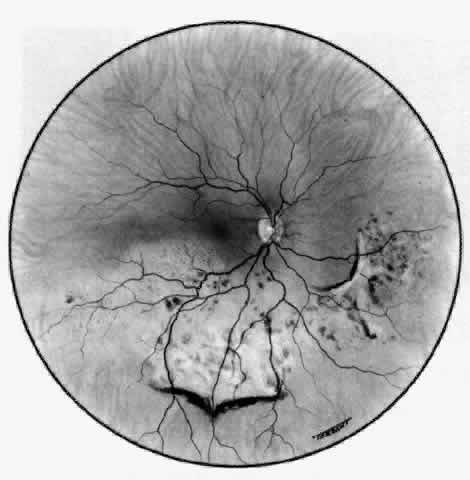

The anterior sclera loses its covering of episclera and develops an area of yellow-white necrotic slough over many months; this eventually separates or is absorbed, leaving the underlying choroid covered by either conjunctiva or nothing at all. As with necrotizing disease, the choroid does not bulge into this ectatic area; but unlike necrotizing disease, spontaneous healing of even small perforations is very limited once the necrotic tissue has been removed (see Fig. 50). Fluorescein angiography is not helpful, except to indicate areas of vascular closure in an otherwise extremely thin, atrophic episcleral tissue.4 The formation of a sequestrum appears to be caused by arteriolar closure as opposed to the venular disease seen in the other forms of necrotizing scleritis. Posterior Scleritis Because the posterior sclera is invisible, the diagnosis of posterior scleritis is made only if the anterior sclera is also involved or some other sign or symptom leads one to suspect it. Posterior scleritis is much more common than previously suspected, as recent clinical and pathologic studies have shown.19,28,29 There are two distinct forms of posterior scleritis. The first is usually associated with an anterior scleritis. This granulomatous disorder, like its anterior counterpart, can be diffuse, nodular, or necrotizing in character and is associated with the connective tissue diseases. The second form occurs in young patients of all races who are 9 to 40 years of age. It is always diffuse in character but is not associated with any systemic disorder. Both forms may cause uveitis if the inflammation affects the ciliary body, and in both forms the patient may develop exudative retinal detachments, choroidal folds, and swelling of the disc (Figs. 51 and 52). The granulomatous type may also involve the structures outside the globe, causing proptosis (Fig. 53), limitation of ocular muscle movement, and, uniquely, retraction of the lower lid on attempted elevation of the eye (Fig. 54). Diagnosis is with B-scan ultrasonography. TREATMENT Scleritis is almost always accompanied by very severe pain that prevents sleep. A response to treatment is heralded by a dramatic relief of pain even though the condition might appear to be getting worse (Figs. 55 through 59). Treatment may be modified with confidence once the pain has disappeared.

COMPLICATIONS Complications occur late in the disease and vary with the severity of inflammation. They occur most frequently in posterior scleritis and in severe necrotizing disease, particularly when the condition has become circumferential and when the inflammation is so severe as to produce secondary intraocular inflammation. Visual Acuity The object of early diagnosis and treatment is to prevent a decrease in visual acuity. The treatment must not produce iatrogenic changes that cause decreased acuity. Over a 3-year period, approximately 27% of the patients who develop this disease will experience a decrease in visual acuity of two or more lines, which can be the result of cataracts and keratitis developing in patients with severe diffuse anterior scleritis. However, over a 25-year period, only 3% have lost useful vision. Increased Scleral Transparency and Thinning Alteration in the collagen and ground substance results in increased scleral transparency. Scleral thinning occurred, particularly in necrotizing disease or scleromalacia perforans. Of these patients, 22% showed increased scleral transparency after the first attack; however, only 6% developed a scleral defect. If scleral defects are small, they will refill with new collagen after treatment; but if they are very large, they may have to be covered with a graft (see Figs. 63 and 64). Uveitis Although roughly 35% of patients with scleral disease show some evidence of cellular activity in either the anterior or the posterior segment, a severe uveitis with a marked flare and heavy cellular response is very unusual. If it does occur, it is a serious sign, and intensive treatment must be instituted at once with systemic steroids. In posterior scleritis, if the granuloma is behind the equator, there may be little or no intravitreal cellular reaction, even though there is a visible granuloma and a retinal detachment. Scleritis occurring between the pars plana and the equator affects the ciliary body, so some inflammatory response occurs. Unless patients with this form of inflammation are treated rapidly, the intraocular pressure sometimes rises disastrously. Most patients with posterior scleritis have high intraocular pressures at some stage in the disease. As the scleral disease is brought under control, the uveitis resolves, leaving anterior and posterior synechiae unless care is taken to prevent them. The inflammation of the pars plana sometimes leads to massive pigment migration at the retinal periphery, leaving a reaction rather like a diathermy or cryotherapy reaction in retinal detachment surgery (see Fig. 52). Glaucoma The intraocular pressure may become raised at any stage of the disease because of an acute congestion of the outflow channels,27 raised episcleral venous pressure, angle closure, or a steroid-induced rise. Therefore, it is important that the intraocular pressure be monitored; 13.5% of all patients with nodular or necrotizing scleritis had a pressure rise, albeit transient, during the course of the disease. Permanent field changes occurred in 5%. Patients with posterior scleritis are particularly prone to develop rises of intraocular pressure. The treatment of the glaucoma is the treatment of the scleritis. Once the scleritis is controlled, the pressure will fall to normal. While the eye is inflamed, particularly if there is a limbitis, acetazolamide should be used to control the intraocular pressure. Should the pressure remain high after the attack, topical timolol can often help to control the intraocular pressure. If control fails, trabeculectomy can be performed successfully in an area of normal sclera and conjunctiva. Cataract Involutional changes that are already present will be increased by the presence of a severe inflammation. However, there is no doubt that the transparency of the lens can be affected directly in patients who have had previously normal lenses and who have developed severe necrotizing scleral disease. If a cataract advances to the extent that it requires removal, the extraction can be performed with use of a corneal section in spite of the presence of scleritis. Healing is a little delayed in some cases, but no operative or postoperative complications have occurred. Cataract extraction and, for that matter, any other surgical procedure can precipitate scleral inflammation in a patient who is predisposed, usually because of circulating immune complex disease. These patients usually have necrotizing scleritis and require vigorous therapy (Fig. 67).23–25,30–33 Retinal Detachment Exudative retinal detachment occurs in patients who have posterior scleritis, and it may, indeed, be the only sign in a very painful eye. The detachment is poorly mobile. A pale gray granuloma can be seen extending from the choroid beneath the retina and is accompanied by a poorly mobile serous detachment that may become total. The scleral granuloma sometimes leaves a permanent, inward indentation of the retina and a subretinal mass, although this does not always occur. An increasing hypermetropia has also been noted; it is of rapid onset (over a period of 1 week) and is caused by the diffuse scleral edema in the early stages of the disease before the detachment of the retina occurs. The exudative detachment usually resolves completely with treatment of the scleritis. However, if the inflammatory changes have affected the macular area, vision will be severely and permanently affected. After resolution, the retina shows a diffuse, heavy pigmentation of the affected area with a “high-water mark” at the edge (see Fig. 52). Patchy changes outside this area do not seem to occur. Surgery is not indicated. Optic Nerve Swelling Granulomatous processes inside the muscle cone or affecting the optic nerve sheaths may be accompanied by edema of the optic nerve (see Fig. 51). Although it is not possible to make a diagnosis of posterior scleritis on the basis of this sign alone, should there be severe pain, proptosis, limitation of movement, and a retinal detachment, a presumptive diagnosis is permissible; however, it can be confirmed only if the anterior sclera becomes involved later in the disease. B-scan ultrasonography is very helpful in defining granulomas involving the sclera and the optic nerve. Swelling of the disc in patients who have presented with anterior scleritis is unusual, but it has occurred in patients in whom it was known that the process had advanced to involve the posterior segment. |